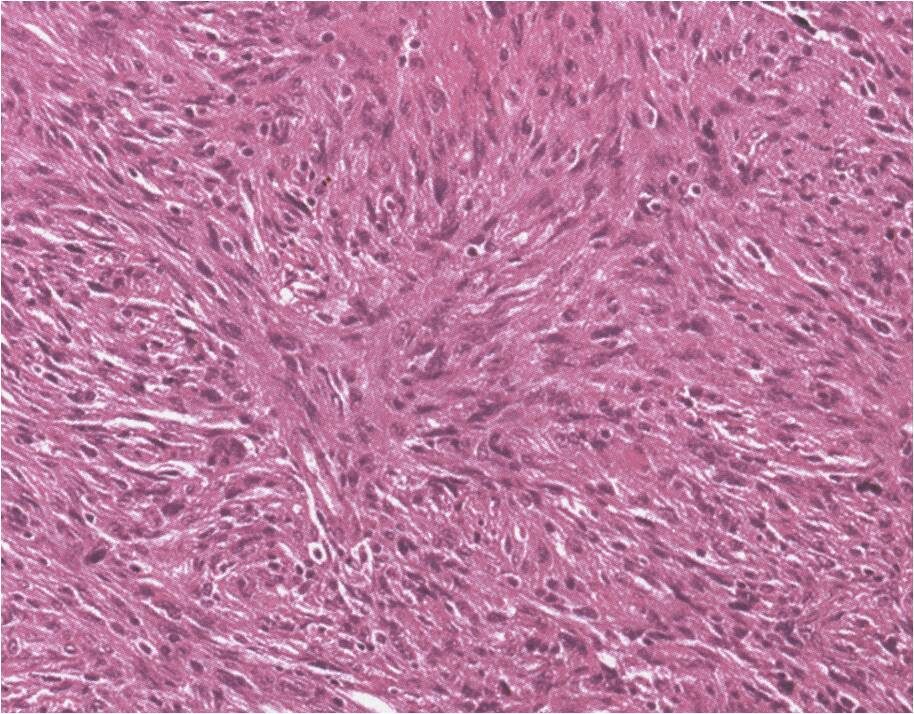

Microscopic (Fig. 9)

• Variable proportions

• Fibrous tissue

• Storiform pattern

• Multinucleated giant cells

• Foam cells

• Occasionally numerous

• No cytologic atypia

• Cholesterol clefts and hemisoderin deposits

• Mitotic figures occasional

• No atypical forms

Fig. 9: Microscopic Pathology of a benign fibrous histiocytoma demonstrates abundant fibrous tissue in a storiform pattern distribution. No atypical forms or mitotic figures are distinguished. Lipid laden macrophages can be seen in a BFH (xanthoma cells)